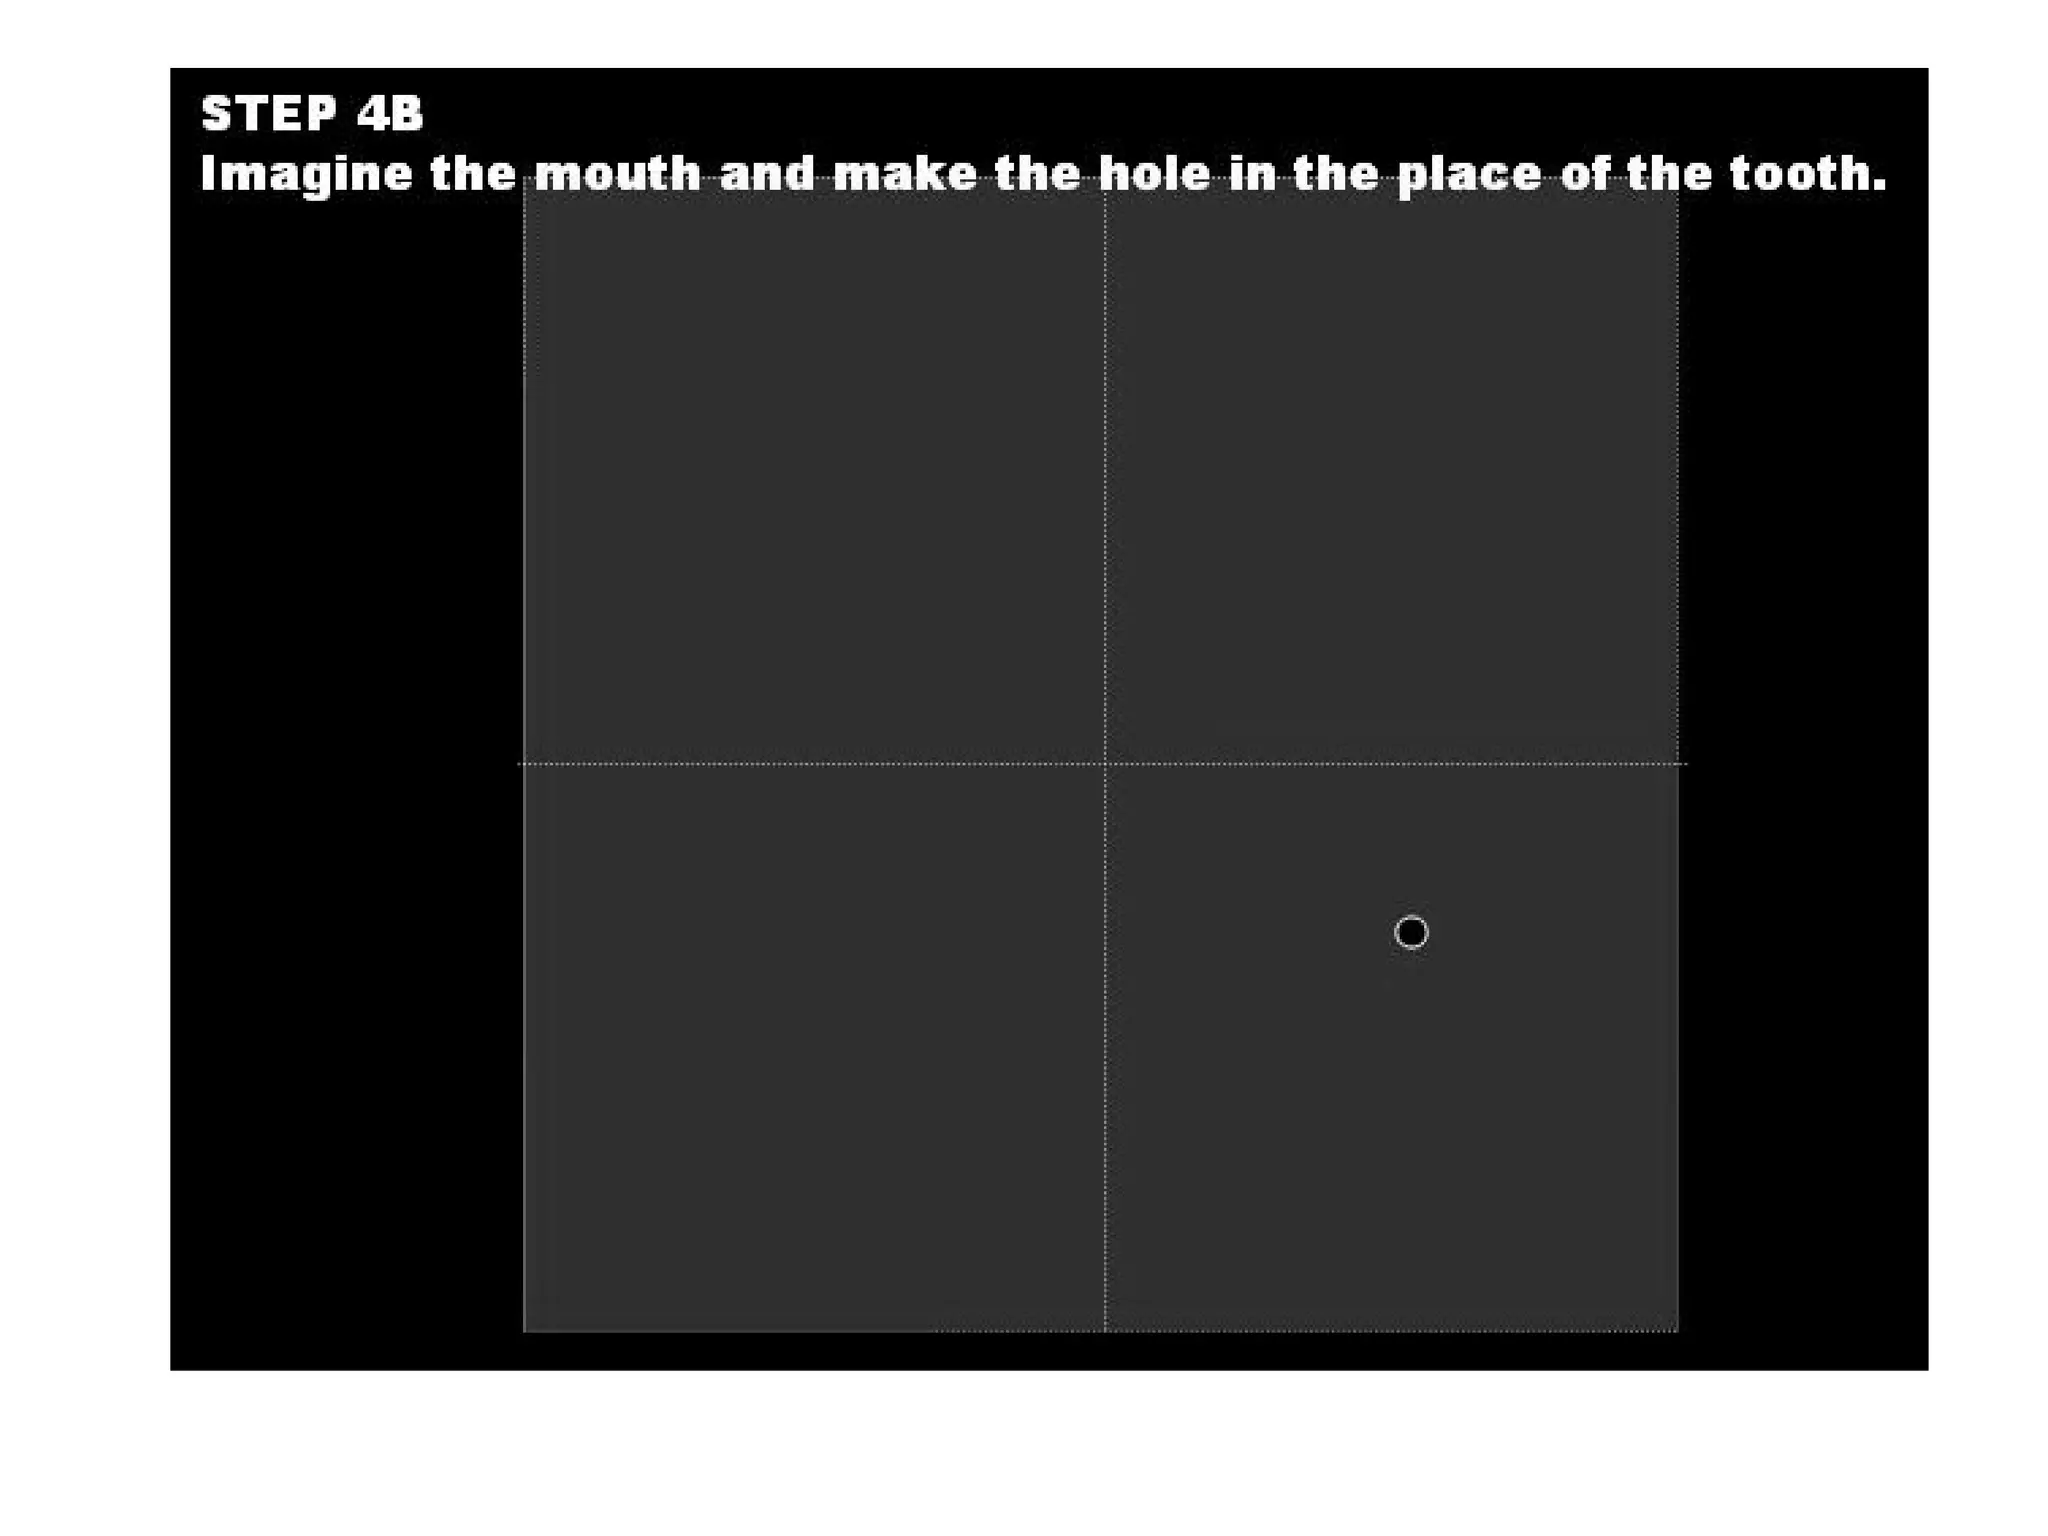

This document discusses the materials and components used for rubber dam isolation in dentistry. It describes the different types of rubber dam materials including color options and napkins to absorb moisture. It also outlines the tools needed such as punches to make holes, templates and stamps to guide hole placement, clamps to secure the dam, and other accessories like wedges and lubricant. Finally, it provides guidance on punching holes for different types of teeth and properly placing clamps in the rubber dam.